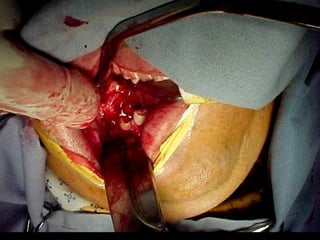

Trismus importante debido a que

El tumor ya rompió el hueso com-

Pacto de la cara interna de la

Mandíbula y empezó a tomar el

Músculo pterigoideo interno y

milohioideo.

Sierra de GigliSierra de Gigli

Luxación de hemimandíbula

Pieza quirúrgica

Plantilla flexible para dar forma previa al implante

Se respetó el cóndilo para anclar la prótesisSe respetó el cóndilo para anclar la prótesis

Límite tumoralLímite tumoral

Area de lisis ósea a nivel de la línea

Miliodes que contracturó los músculos

Milohioideo y pterigoideo interno

Dificultando la deglución y determinando

Trismus importante.

Pieza en proceso de examen por histopatología

Dr. Ismael Espejo Plascencia Patólogo